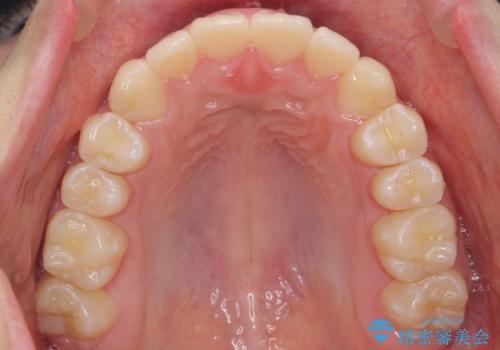

中学生のマウスピース矯正 歯を抜かずにキレイに

- 出っ歯を主訴に来院。

(1)インビザラインで歯を少し削って並べる。歯は抜かない。・・・歯を抜かなくて良い。歯磨きが楽、装置も目立たない。通院は3ヶ月に1回。

非抜歯ながらも、矯正用のインプラントを使用し、出来るだけ前歯を下げるように工夫して治療しました。

治療結果にはお母様、ご本人も含め、大変喜んでいただきました。

歯を抜かずに治療しましたが、治療前後で口元が悪化しないように治療することができました。